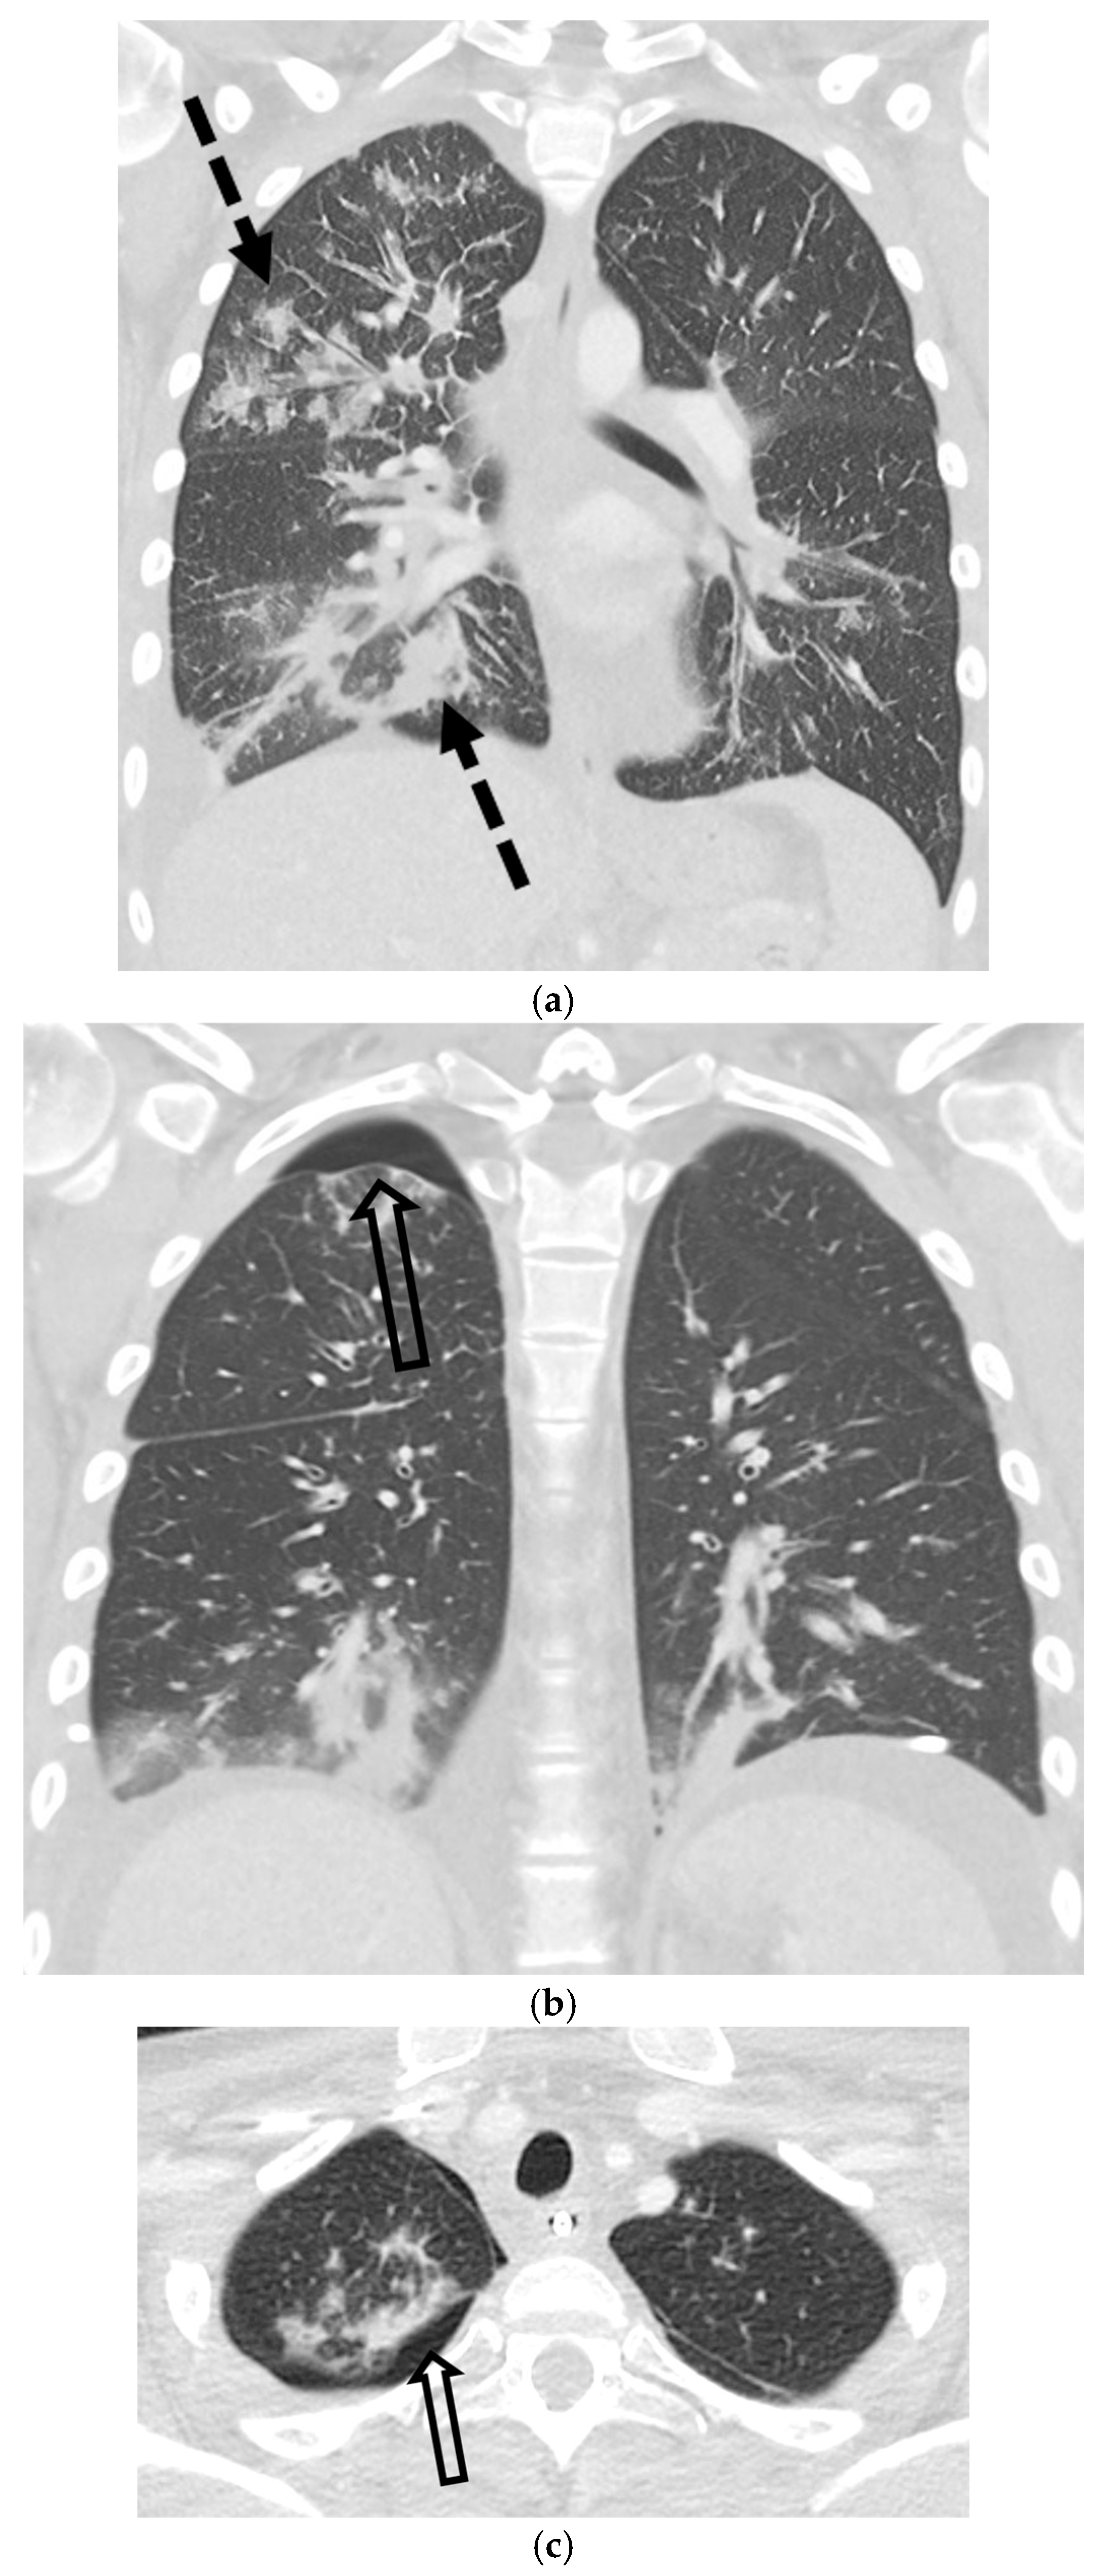

5.3. Malignancies

5.5.1. Pulmonary Langerhans Cell Histiocytosis (PLCH)

5.5.2. Lymphangioleiomyomatosis (LAM)